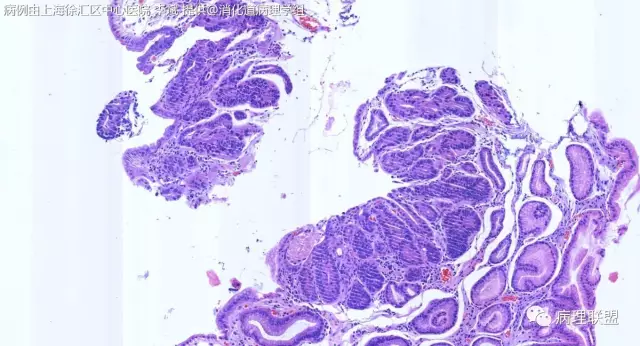

F-56 胃窦粘膜活检(低级别 vs 高级别)

女,56岁,胃窦粘膜活检(病例由上海徐汇区中心医院 李斌 提供,致谢!)

@李斌,高级别,腺体结构乱复杂,核异型性大,极向乱

@左淑英 子宫内膜受激素周期影响,腺体结构和上皮变化比较大,消化道受损伤、炎症等影响比较大,同样要看结构、看细胞,但标准确实不大一样。虽然具体病例需要具体分析,但我感觉在胃肠道,对于判断时感觉模棱两可的病例,表面成熟现象是区分反应性增生和低级别异型时可重复性相对比较好的指标;核极向是区分高低级别异型增生时可重复性相对比较好的指标。供参考